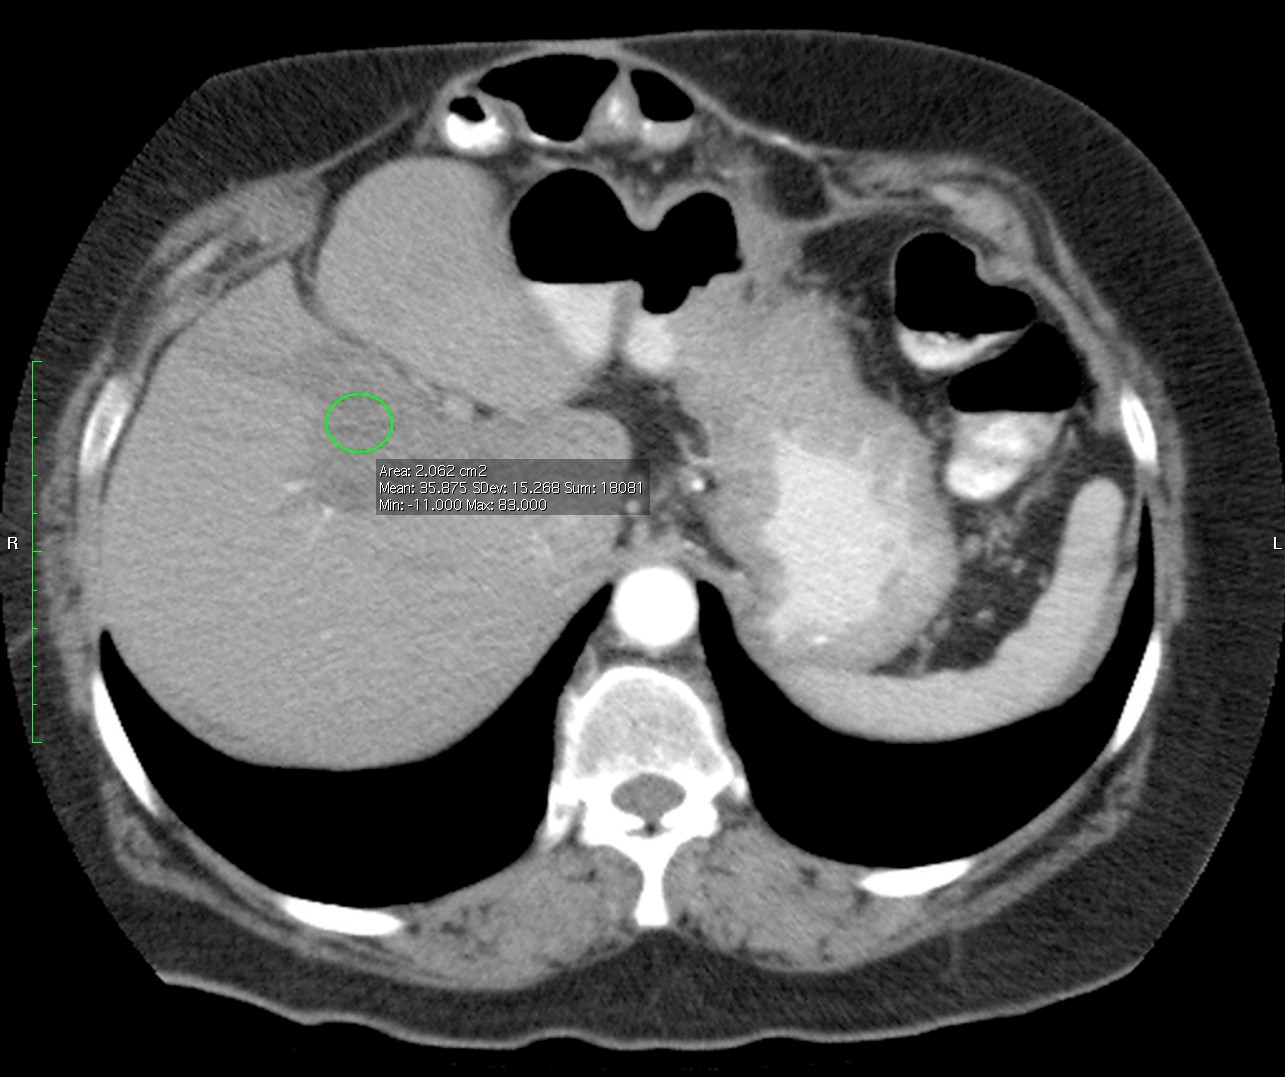

Paciente de 66 años con antecedente de pancreatitis, tomografía control.